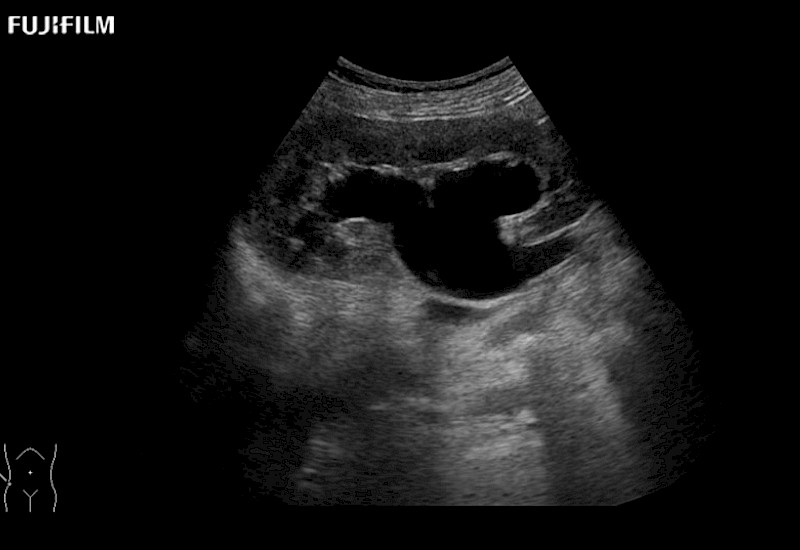

Our dedication to Laparoscopic Surgery allows us to offer superior image quality, outstanding system reliability and intuitive use of cutting edge technology.